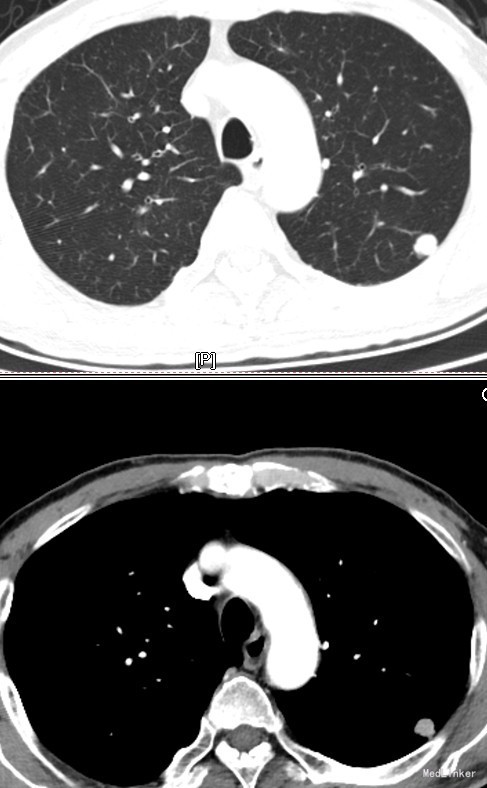

入院后复查胸部CT时发现左肺新发肿物,后转入我科,行详细术前检查后,行胸腔镜左肺上叶肿物切除术。术后病理回报:(左肺结节)肺癌(中-低分化),分类困难。患者顺利出院。